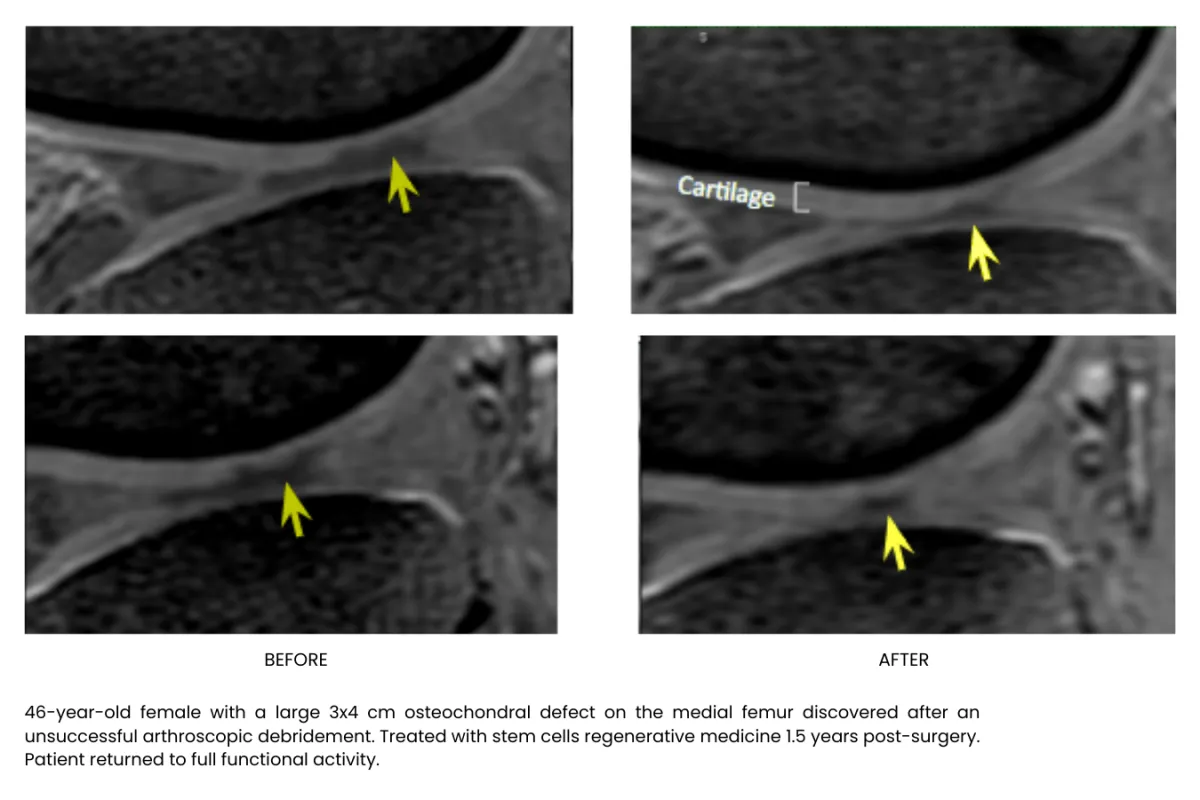

Millions of stem cells delivered precisely in the injured area building up tissue, recovering and freeing your from pain, without surgery or long recoveries.

Stem cell therapy is a regenerative treatment that uses specialized healing cells to help repair damaged tissue, reduce inflammation, and support your body’s natural healing process. It’s commonly used for joint pain, arthritis, and chronic musculoskeletal conditions.